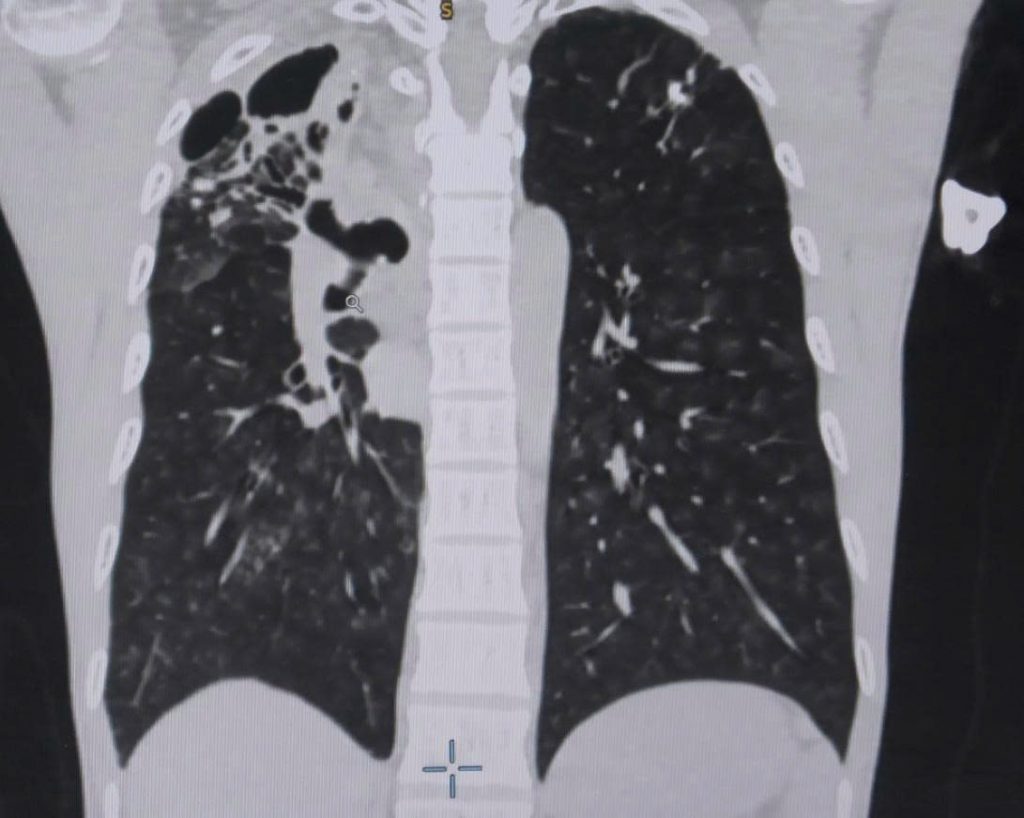

Tiếp nhận người bệnh tại khoa Cấp Cứu Bệnh viện Đa khoa Xuyên Á, các bác sĩ đã chỉ định cho anh H. nội soi phế quản, chụp CT ngực có thuốc cản quang để đánh giá tình trạng bệnh lý phổi. Kết quả ghi nhận phổi bên phải của anh H. có tình trạng hang lao cũ và có nhiều tổn thương giãn phế quản, phì đại động mạch phế quản. Đây là nguyên nhân của tình trạng vỡ mạch máu phế quản – một bệnh lý nguy hiểm có thể gây suy hô hấp dẫn đến đe dọa tính mạng, thậm chí khi máu tràn vào đường thở, bệnh nhân có thể ngạt thở ngay lập tức, chưa kể mất máu nhanh chóng.

Hình ảnh CT phổi cho thấy bệnh nhân bị vỡ mạch máu phế quản